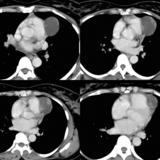

Part'l absc peric CT

Date: 07/23/2006

Views: 3171